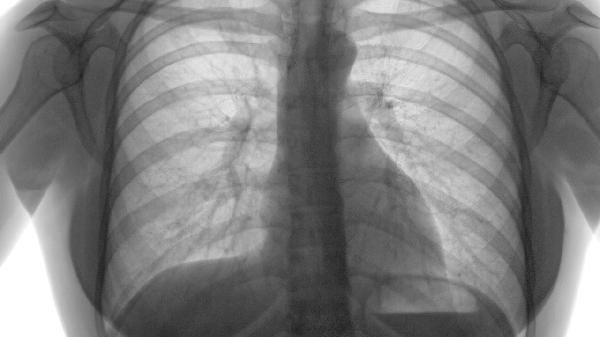

直径小于5毫米的稳定肺气肿灶通常无需特殊治疗,定期随访观察即可。若病灶超过10毫米或呈进行性增大,可能提示肺组织破坏加重,需考虑干预措施。影像学检查显示多发性肺大泡时,即使无症状也建议评估手术指征。

肺功能检查显示FEV1/FVC比值正常者可暂缓治疗。若出现中度以上阻塞性通气功能障碍FEV1占预计值60%以下,需进行长期氧疗或无创通气支持。弥散功能显著下降者可能需肺康复训练。